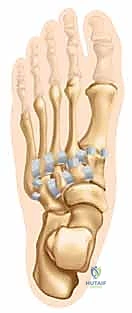

مركب مفاصل رسغ القدم (TMT)

تُشير إصابة ليزفرانك إلى أي ضرر يصيب العظام أو الأربطة في مركب مفاصل رسغ القدم (Tarsometatarsal Joints) والمفاصل بين العظمات المسمارية (Intercuneiform Joints). سُمي هذا المفصل على اسم الجراح الفرنسي "جاك ليزفرانك دي سان مارتن" الذي خدم في جيش نابليون، والذي لاحظ هذا النمط من الإصابات لدى الفرسان الذين يسقطون من خيولهم بينما تبقى أقدامهم عالقة في الركاب.

القوس الروماني وحجر الزاوية (The Roman Arch and Keystone)

تتكون المفاصل الرسغية المشطية الثلاثة الإنسية (الداخلية) من العظمات المسمارية الإنسية والمتوسطة والوحشية، التي تتمفصل مع قواعد الأمشاط الأول والثاني والثالث.

في المقطع العرضي، تشكل هذه العظام شكلاً شبه منحرف فريدًا، مكونة ترتيبًا مقعرًا من الناحية الأخمصية (السفلية)، يشبه إلى حد كبير القوس الروماني الكلاسيكي في الهندسة المعمارية. توفر هذه البنية العظمية المتأصلة ثباتًا كبيرًا للقدم وتسمح لها بتحمل أضعاف وزن الجسم.

يُعتبر عظم المشط الثاني هو "حجر الزاوية" (Keystone) المطلق لهذا القوس؛ فهو يقع محشوراً بين العظمات المسمارية الإنسية والوحشية في المستوى المحوري، ويقع في قمة القوس في المستوى الإكليلي. إن ثبات هذا العظم (المشط الثاني) حاسم لمركب منتصف القدم بأكمله. أي إزاحة ولو بمليمترات قليلة في هذا المشط تؤدي إلى انهيار القوس بأكمله.

المثبتات الرباطية القوية (Ligamentous Stabilizers)

لا يعتمد ثبات منتصف القدم على العظام فحسب، بل يتم تثبيت مفاصل رسغ القدم بواسطة شبكة معقدة من الأربطة القوية الظهرية (العلوية) والأخمصية (السفلية). في الإصابات الرباطية البحتة، يعتمد الثبات على سلامة الأربطة الرسغية المشطية الأخمصية. إذا تمزقت هذه الهياكل القوية، فإن الإصابة تكون غير مستقرة بطبيعتها وتتطلب تدخلاً جراحياً.

- رباط ليزفرانك (Lisfranc Ligament): هذا هو النجم الرئيسي والمحور الأساسي في هذه الإصابة. هو رباط قوي جداً، يمتد بشكل مائل من الجزء الأخمصي (السفلي) للعظم المسماري الإنسي إلى قاعدة المشط الثاني. تعتبر سلامته عاملًا حاسمًا في تحديد ثبات منتصف القدم. إذا تمزق هذا الرباط، تنفصل قاعدة المشط الثاني عن العظم المسماري، مما يؤدي إلى عدم استقرار القدم بالكامل.

- الأربطة بين الأمشاط (Intermetatarsal Ligaments): توفر الأربطة بين الأمشاط الظهرية والأخمصية مزيدًا من الثبات بين قواعد الأمشاط من الثاني إلى الخامس.

- نقطة الضعف التشريحية: الأهم من ذلك، لا توجد أربطة بين الأمشاط الأول والثاني، وهي نقطة ضعف تشريحية رئيسية تجعل هذه المنطقة عرضة للانفصال والإصابة عند التعرض لضغط شديد.

وظيفة الأعمدة الثلاثة في القدم (The Three Columns)

من الناحية الوظيفية والجراحية، يقسم الأستاذ الدكتور محمد هطيف منتصف القدم إلى ثلاثة أعمدة ميكانيكية حيوية:

- العمود الإنسي (الداخلي): يتمثل في مفصل رسغ القدم الأول والمفاصل الزورقية-المسمارية الإنسية. يتحكم في حركة إصبع القدم الكبير وهو حيوي لعملية الدفع أثناء المشي.

- العمود الأوسط: يتمثل في مفاصل رسغ القدم الثاني والثالث، والمفاصل بين الزورقي والعظمات المسمارية المتوسطة والوحشية. هذا العمود صلب للغاية ومصمم لنقل القوة.

- ملاحظة جراحية هامة: يتمتع العمودان الإنسي والأوسط بحركة محدودة متأصلة ويُعتبران غير أساسيين لوظيفة الحركة المرنة للقدم، مما يجعلهما مناسبين لعملية دمج المفصل (التحام أو Arthrodesis) كخيار علاجي ممتاز إذا لزم الأمر دون التأثير بشكل كبير على مشية المريض.

- العمود الوحشي (الخارجي): يتمثل في مفاصل رسغ القدم الرابع والخامس (المتصلة بمكعب القدم). تتمتع هذه المفاصل بحركة متأصلة أكثر بكثير، وهي ضرورية لتكيف القدم مع الأسطح غير المستوية. لذلك، يتجنب الجراحون الماهرون مثل الدكتور هطيف دمج هذا العمود إلا في الحالات القصوى جداً، ويفضلون التثبيت المرن.